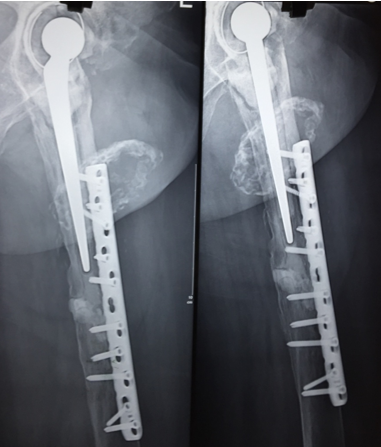

In a series of delayed union with internal fixation over 47 patients regardless of the fracture sites communition or inadequate fixation, had union in all patients including a case of infected nailing of femur. These patients had reported to Dr. S S Jha three to seven months after internal fixation at other centers. None of these patients were willing to submit themselves for further surgical intervention. Teriparatide 20mcg daily through subcutaneous route was started in all patients with adequate supplementation of vitamin D and calcium. Evident radiological bony union was perceptible after three months with clinical improvement in the initial presenting symptoms of the patients and the osseous consolidation was invariably observed radiologically within four to six months. It was only in six patients that Teriparatide was continuously used for one and half years for reasons of general debility, elderly age and osteoporosis. Radiographs of three difficult cases are being displayed from the series.

Case 1([Figure 1], [Figure 2], [Figure 3], [Figure 4], [Figure 5], [Figure 6], [Figure 7], [Figure 8], [Figure 9])

- Case 1([Figure 1], [Figure 2], [Figure 3], [Figure 4], [Figure 5], [Figure 6], [Figure 7], [Figure 8], [Figure 9])